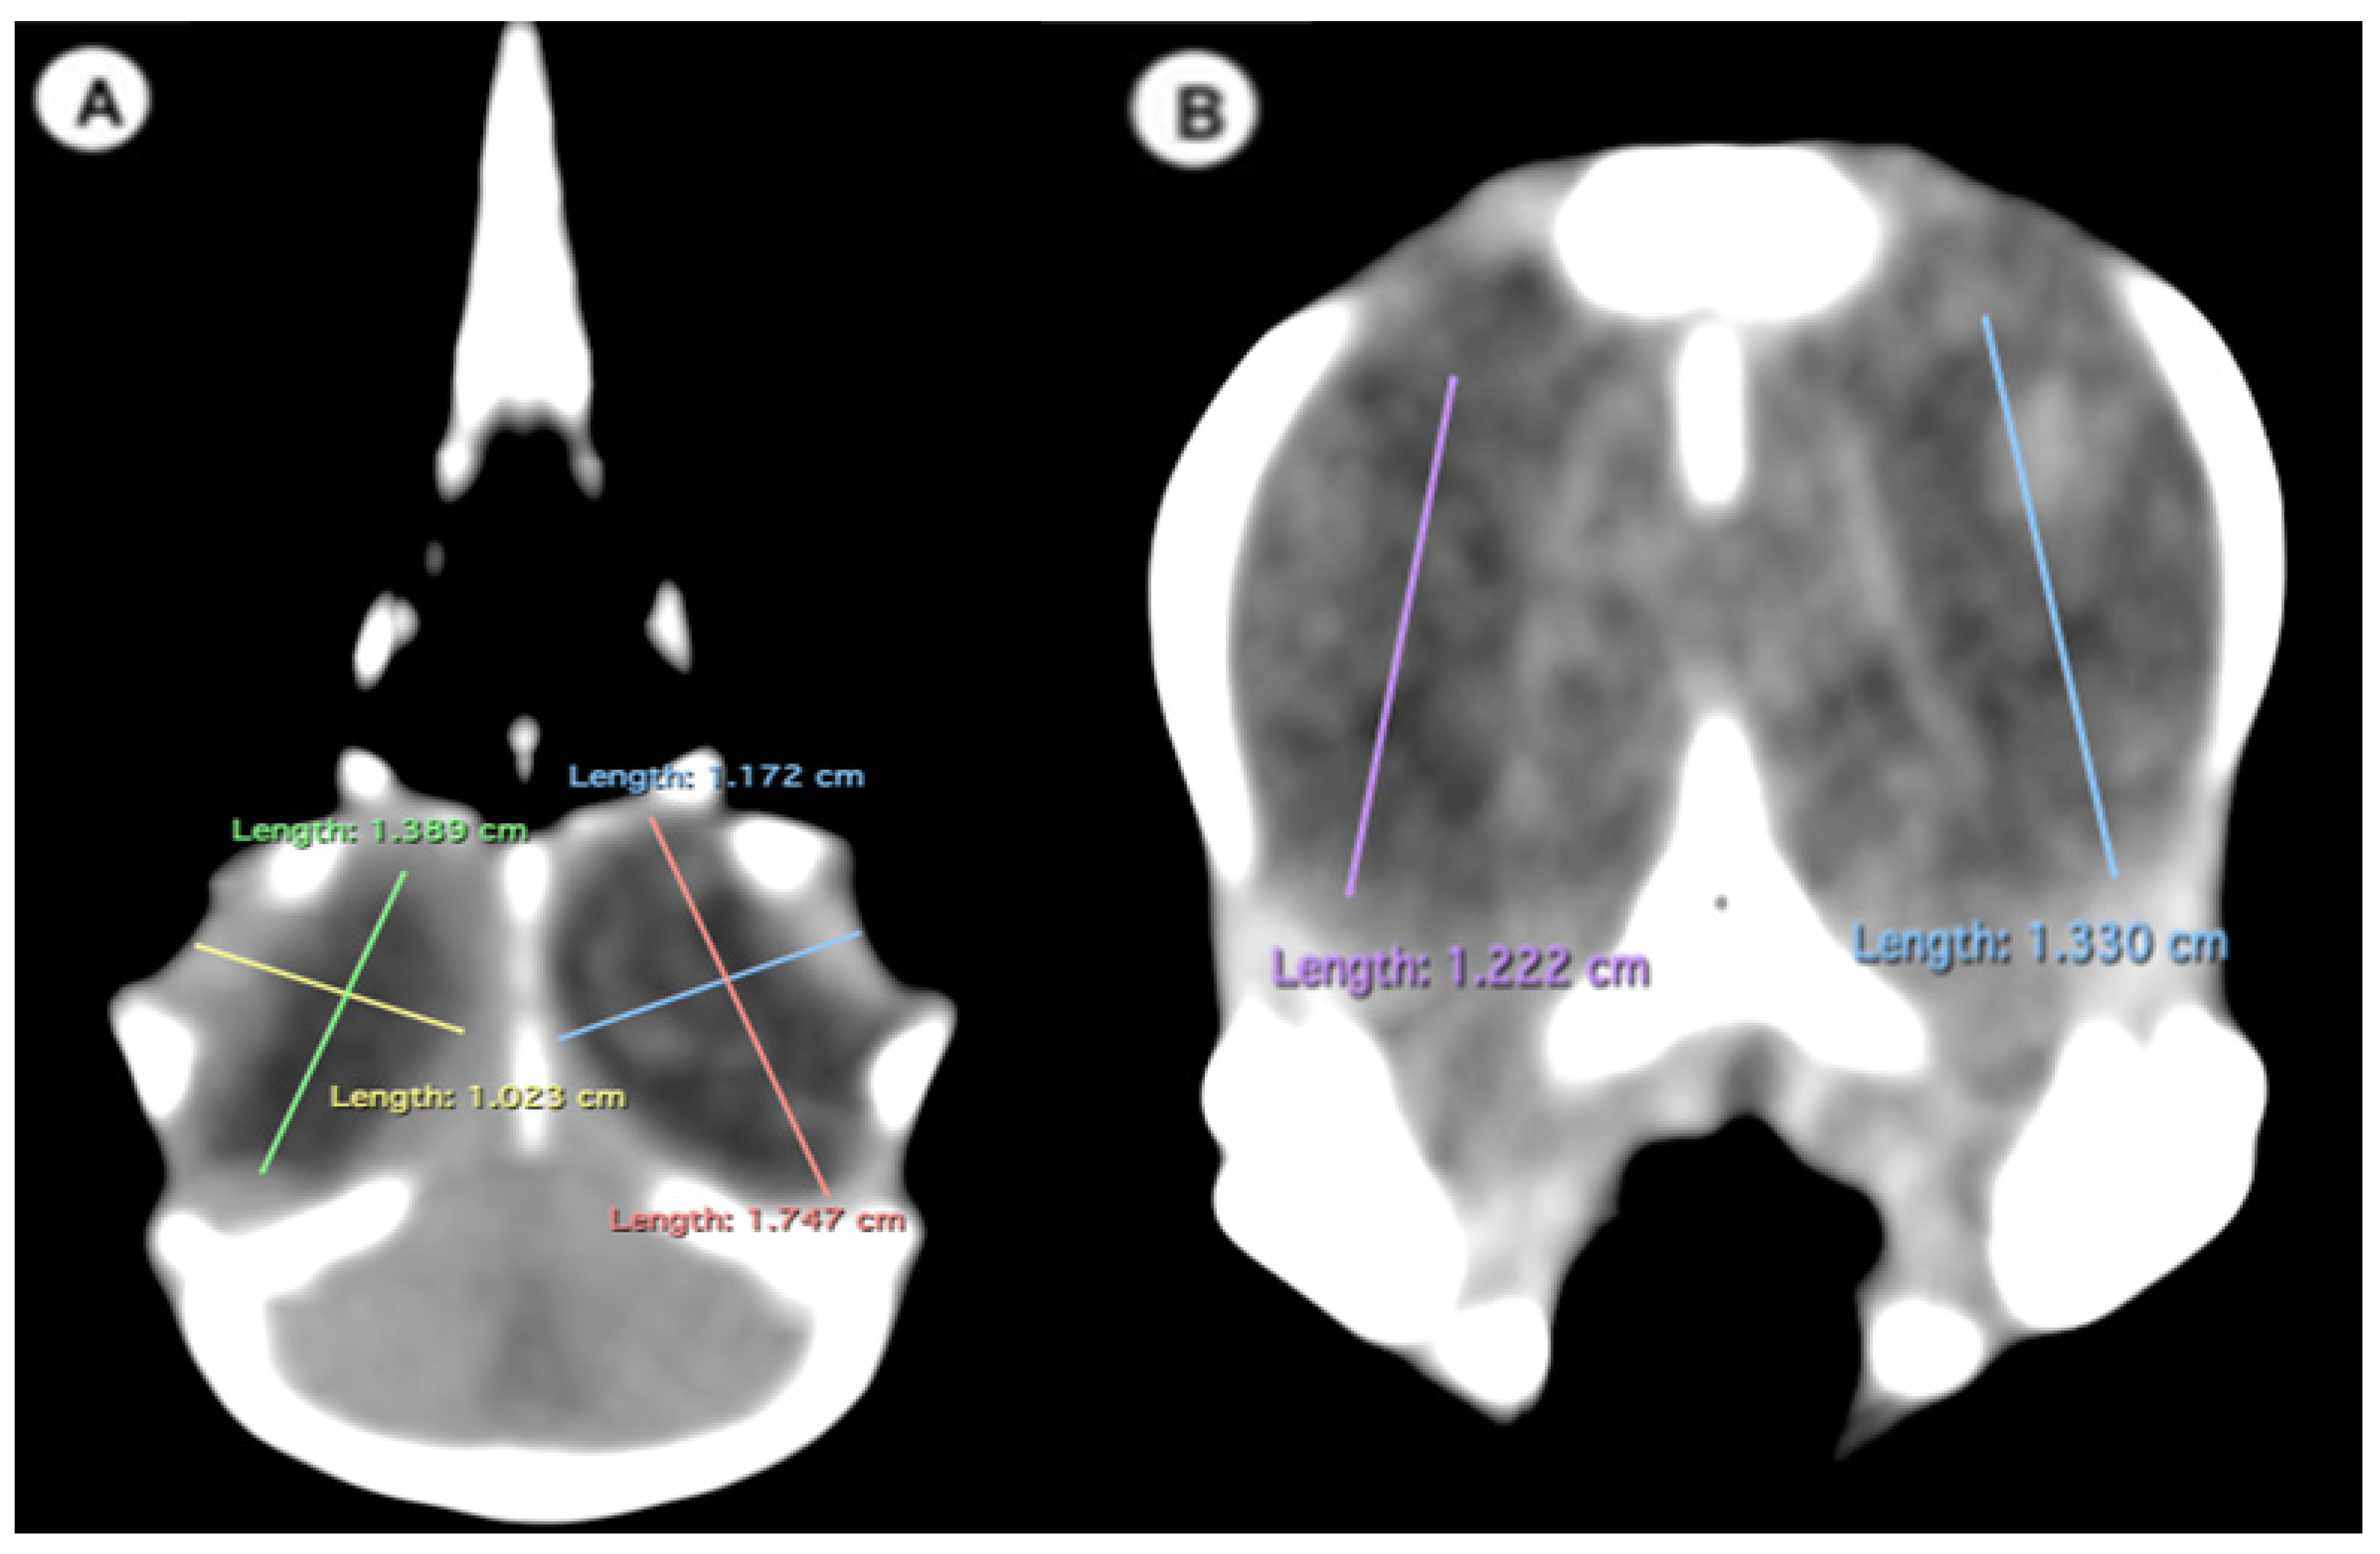

- Width of the ocular bulb: This measurement represents the lateromedial length of the ocular bulb, extending from the os lacrimale to the inner face of the os frontale (Figure 3A);

- Length of the ocular bulb: This measurement refers to the distance between the most rostral and caudal portions of the ocular bulb, spanning from the septum interorbitale to the processus antorbitalis (Figure 3A).

- Attenuation of the sclerotic ring and lens: This measurement was taken in the dorsal area and expressed in Hounsfield Units, providing information about the radiodensity of the sclerotic ring, lens, and vitreous humor (Figure 4).